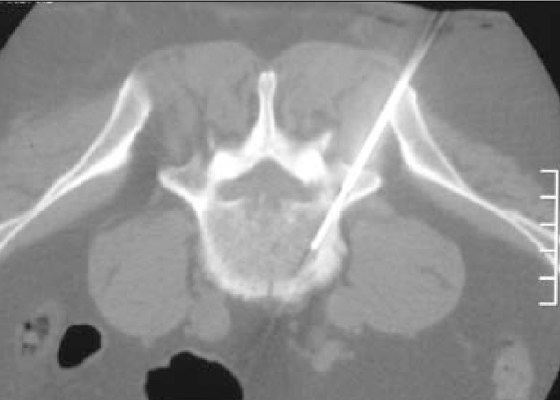

P.E.T. Scan March 2017 (P.E.T. Number 8)

Definitely setting unbreakable records this time with Scans. Had the scan but I was unable to get the results prior

When it started to go wrong a new Lymphoma site to middle spine Routine double checking of scans is now